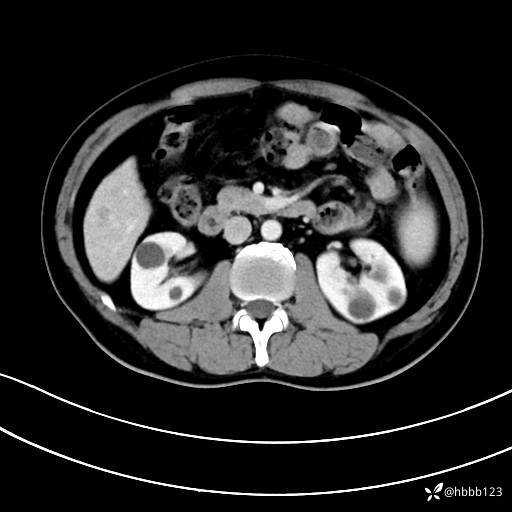

静脉期:

延迟期: